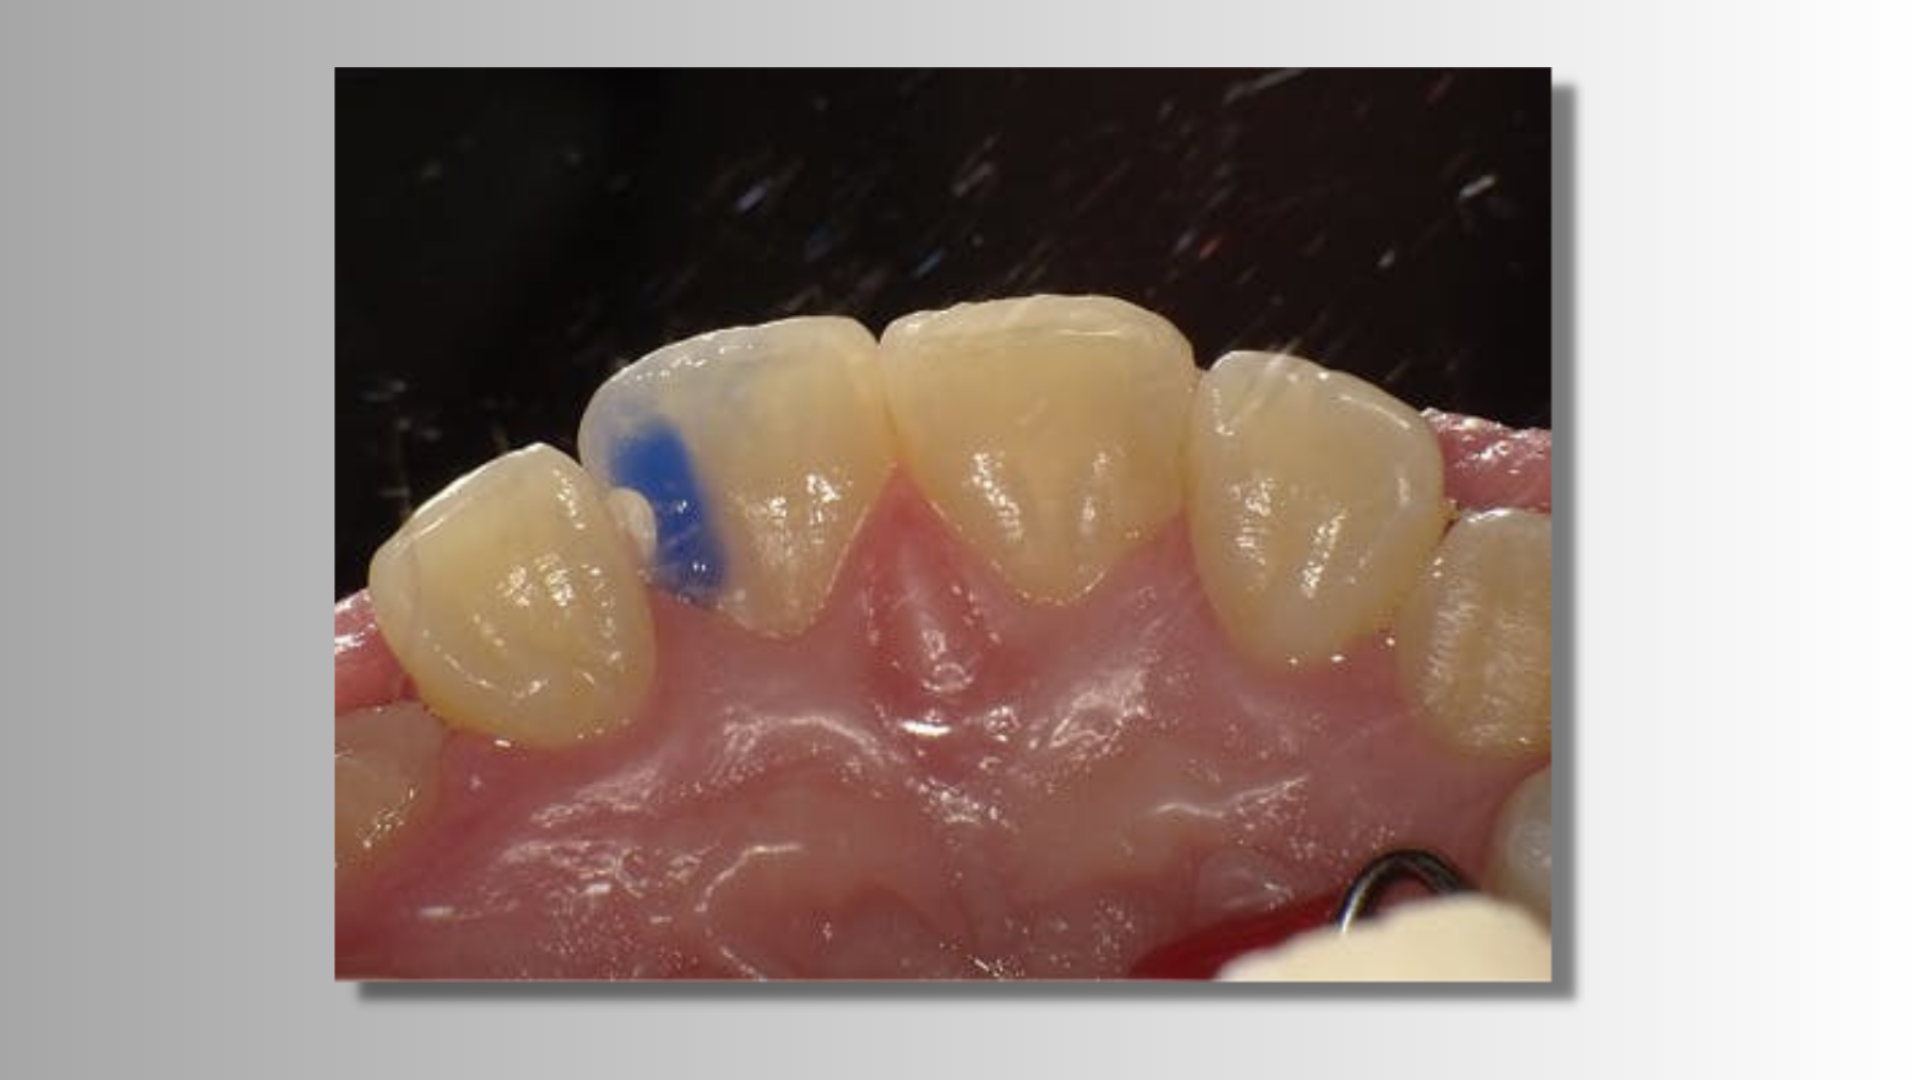

This session brings Dr. Ron Kaminer (dentist and lecturer) together with Gregor Connell (materials specialist, educator, and lecturer) to discuss several materials. The category/class of universal adhesives has rapidly become the adhesive system of choice for many clinicians around the world. An open discussion will take place surrounding what makes these adhesives so versatile in today's modern practices and it will involve Dr. Kaminer’s personal experiences using this class of adhesive system with an explanation as to how they are able to accomplish these functions, from a more scientific perspective.

The recent upswell in biomimetic dentistry has found a growing population of clinicians searching for more tooth-like restorative materials. A review of one of the most tooth-like restoratives based on how closely it matches the Key Clinical Performance Indicators (KCPI) that align with “tooth-like” behavior and performance will be shared and discussed during this course.